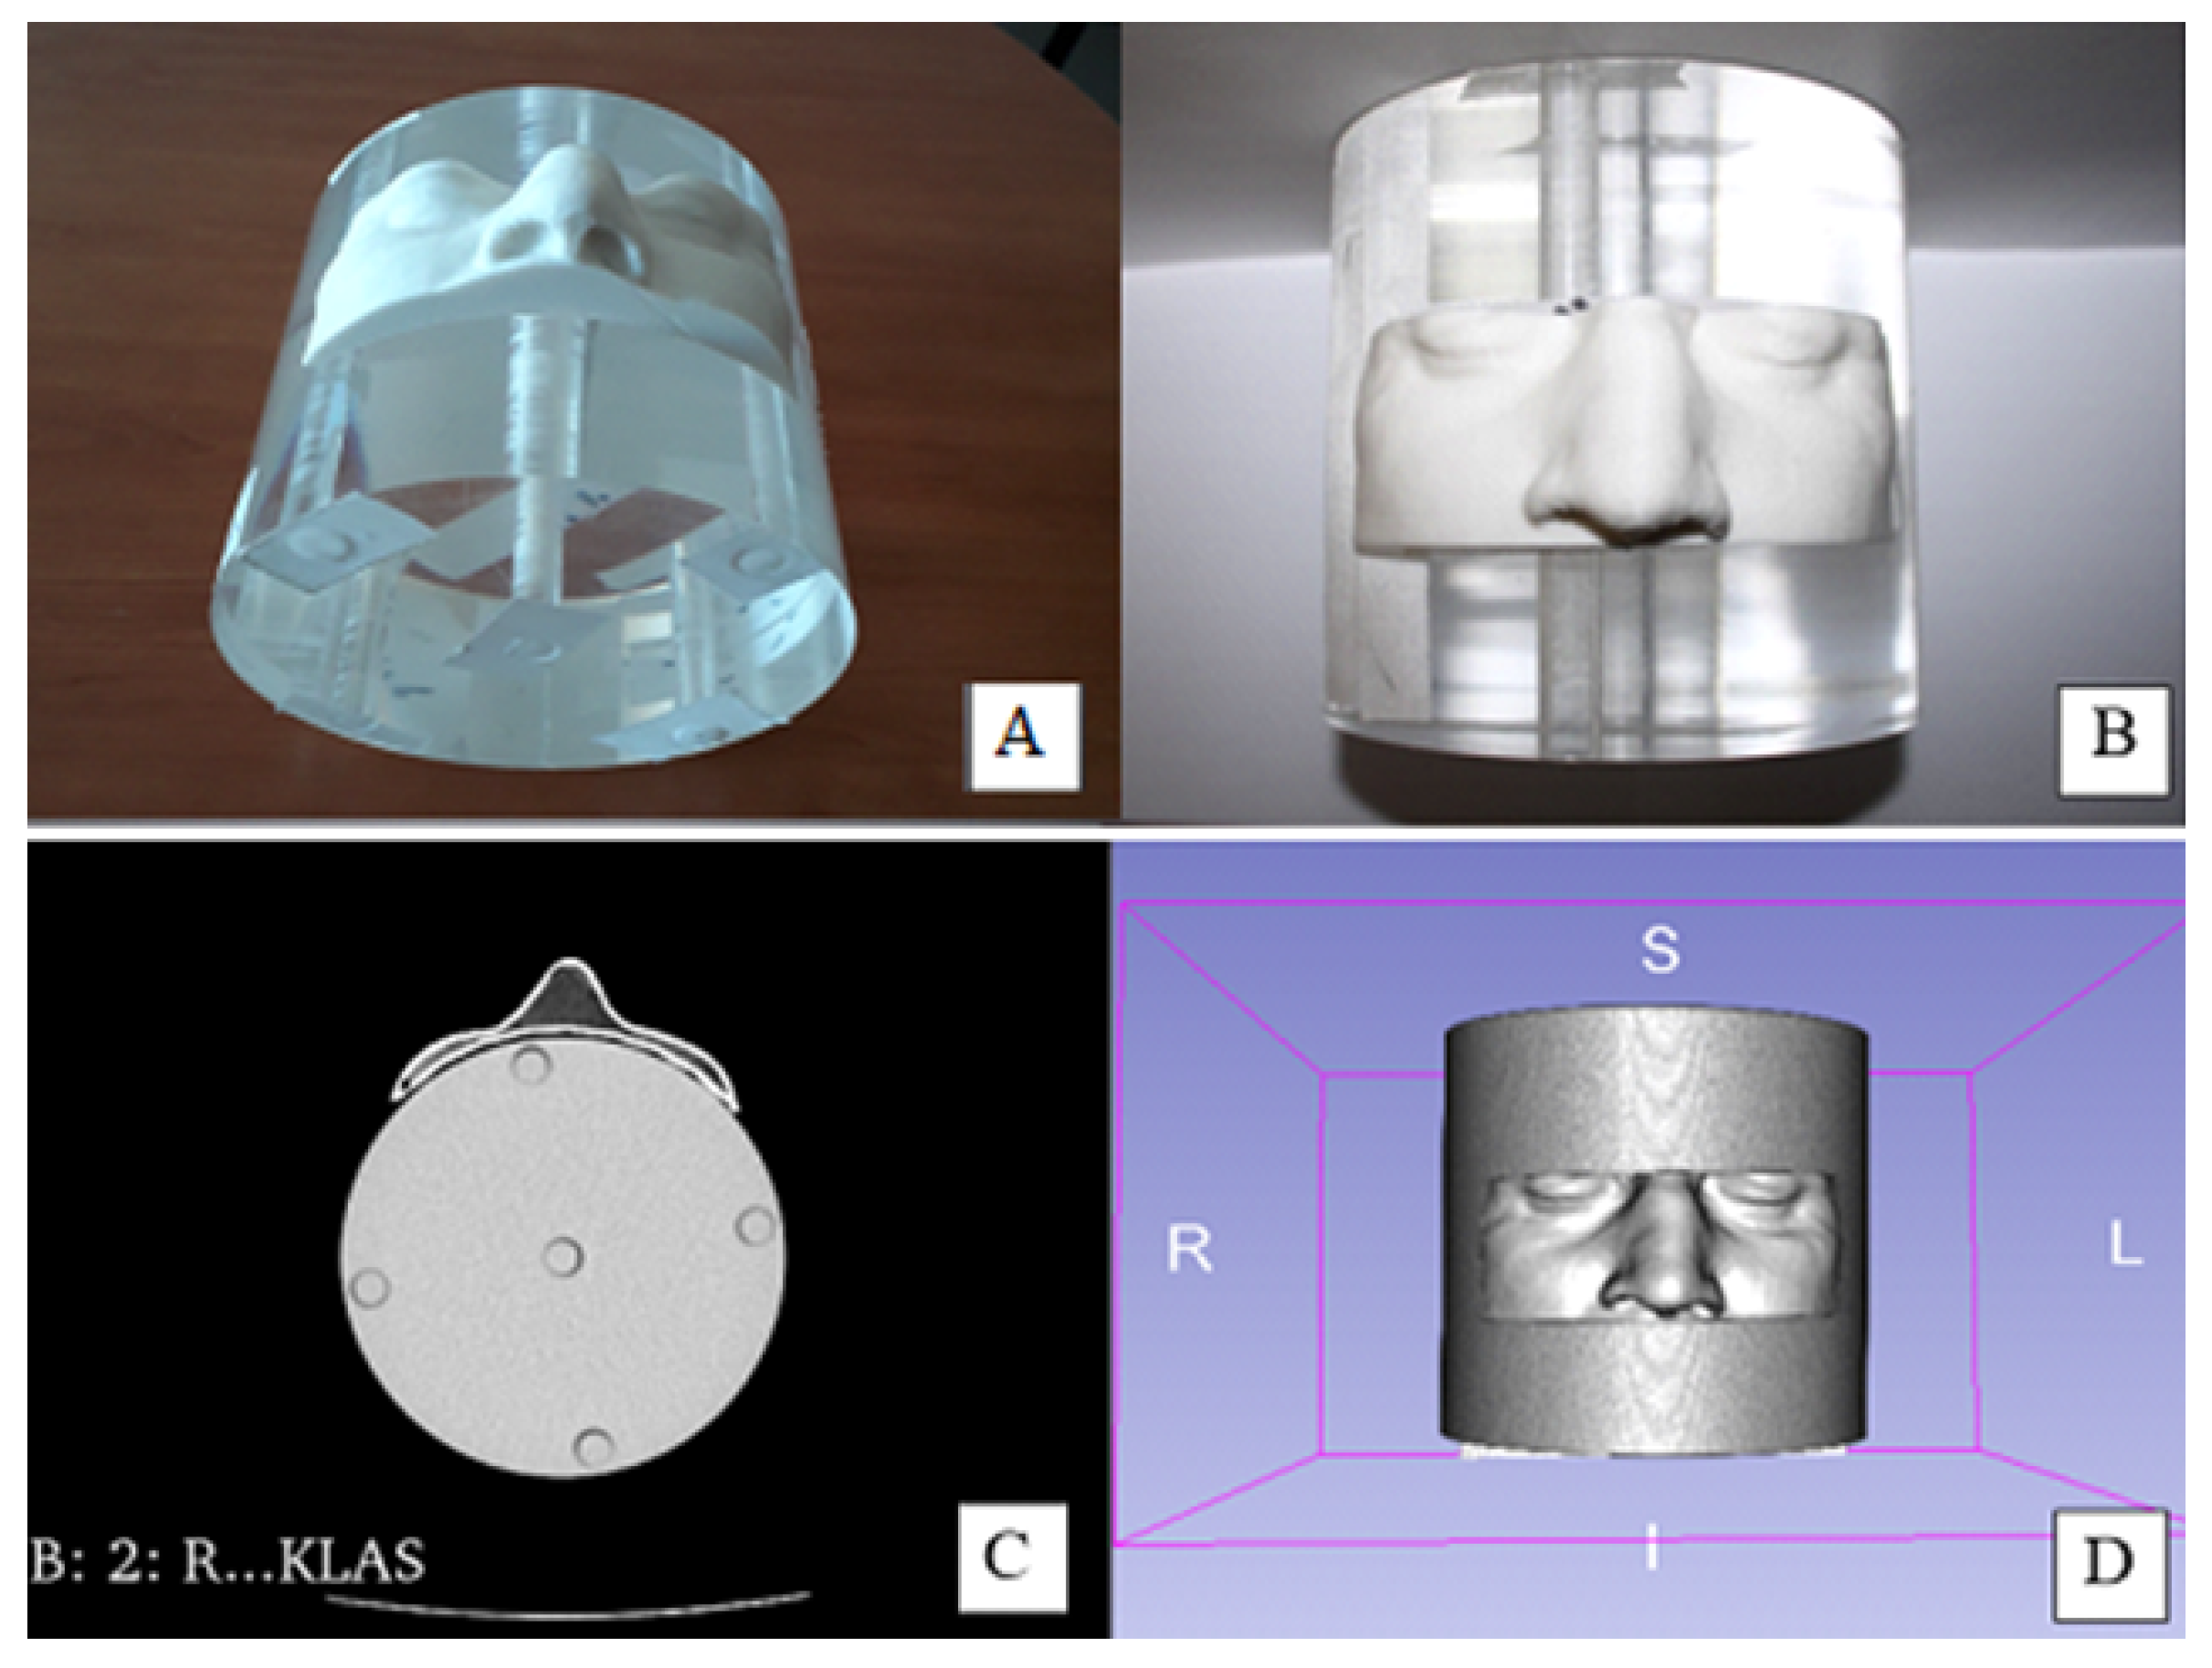

2.1. Development of Personalized 3D Devices